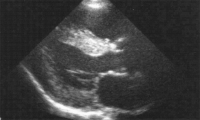

Eine seltene Ursache der hypertrophen Kardiomyopathie – Morbus Fabry // A Rare Cause of Hypertrophic Cardiomyopathy: Fabry’s Disease

Journal für Kardiologie - Austrian Journal of Cardiology 2018; 25 (7-8): 181-184 Volltext (PDF) Summary Abbildungen